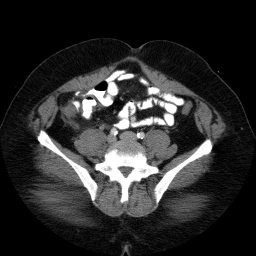

This is an image from a contrast enhanced abdominal CT.

These are images from a contrast enhanced abdominal CT.

Fluid in the right paracolic gutter, and a thickened, inflamed appendix with thickening of the adjacent cecal wall.

Differential: Acute appendicitis is by far the most likely diagnosis.

No appendicolith is seen in this case.

The appendix is normally less than 7 mm in diameter, or if fluid filled, the wall can be up to 3mm thick. This appendix is distended, and the adjacent stranding and fluid indicates the inflammatory process which is causing peritoneal irritation and pain. Here is a series of images showing a normal appendix using similar technique. Note the thin walls of the normal appendix.